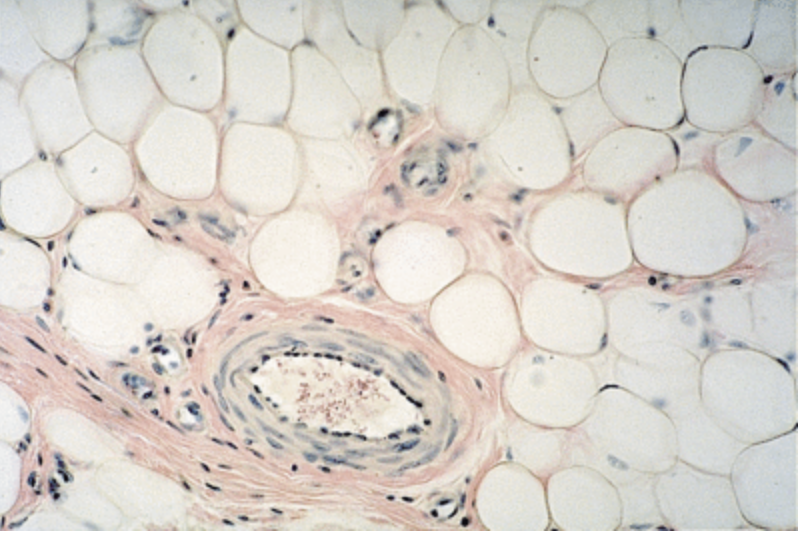

Identify the blood vessel

Adipocytes usually appear under the microscope as empty spaces because fat does not survive the usual slide preparation process. Notice the flattened cell nucleus adjacent to the open space. The blood vessel is sometimes an empty space surrounded by numerous flattened (squamous) nuclei, plus muscle and/or connective tissue depending on how large the vessel is.